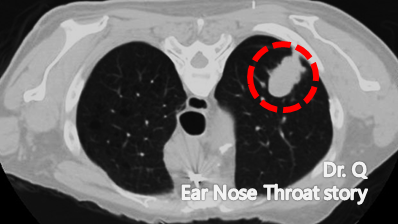

CT 검사에서 발견된 폐가 암 덩어리

폐암은 초기 증상이 있을 때 빨리 발견하는 것이 무엇보다 중요한 암입니다.